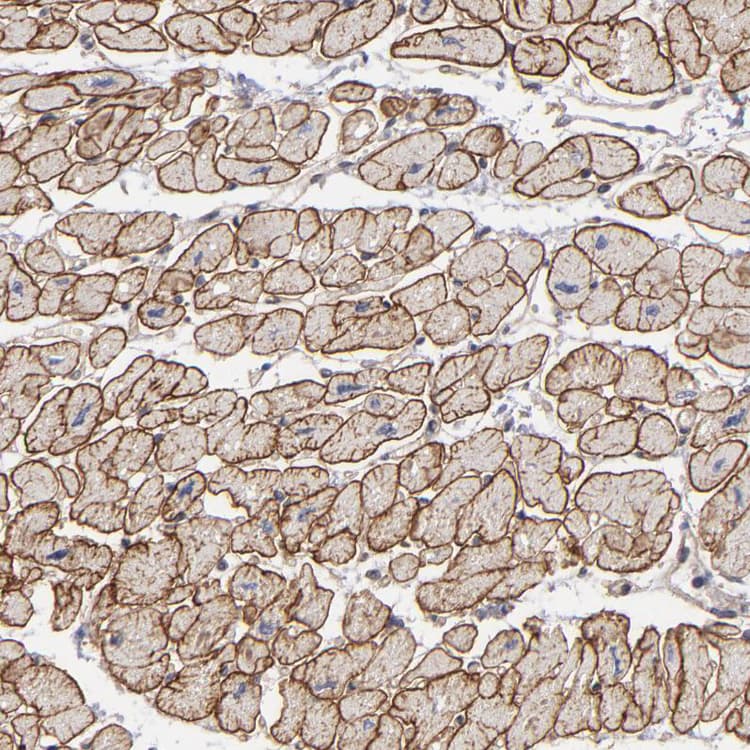

Rabbit Polyclonal Dystrophin antibody. Suitable for IHC-P and reacts with Human samples. Immunogen corresponding to Recombinant Fragment Protein within Human DMD aa 150-350.

Applications IHC-P

Species Reactivity Human